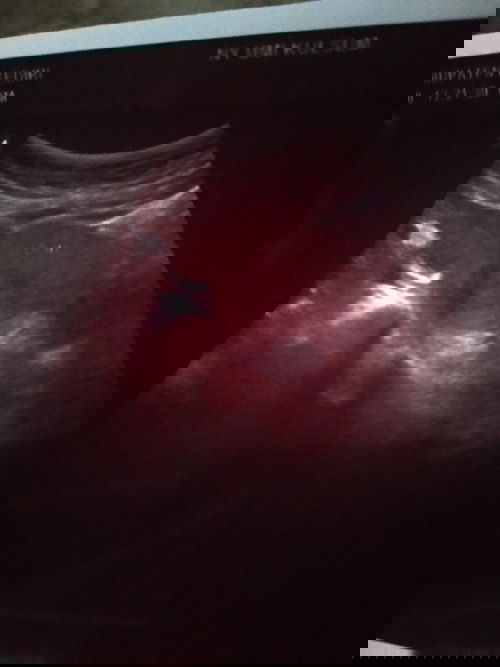

Mau tanya dong bun..ad yg prnah ngalamin kyak sya.sya hamil di usia khamilan 6wek aq kluar flek 2hri.dan sma bidan di suruh usg.aq usg pas udh gk flek lgi.tpi pas usg kta dokternya tidk tumbuh janinya.doktrny tany sma sya udh di tp ap blm.sya jawab udh 2x tp dok dan hsilnya positif.trus dksih obt penguat.susternya di luar bilang ktny hsil usg blm nampak.jdi dsuruh nunggu sbulan.krna sya ingat kta bidan dsuruh tp semingguan lgi.akhirnya sya tp hri ini hsilnya garis 2 bun..gmn solusinya bun?#bantusharing